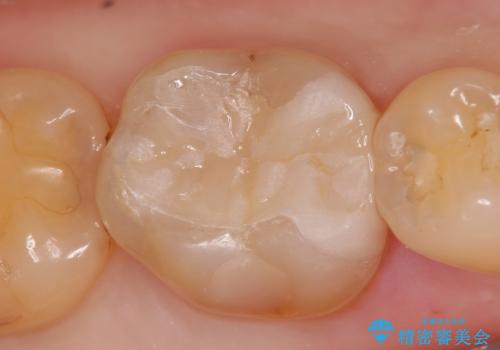

- 右下の銀歯を白くしたいといらっしゃった方の症例です。

銀歯を除去し、セラミックインレーによる修復を行いました。